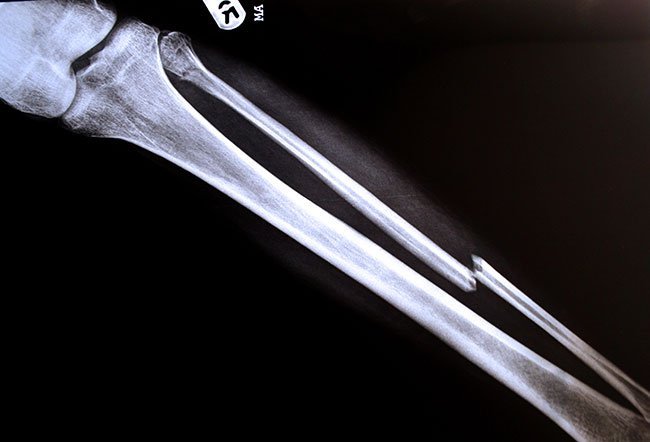

The fibula is the long, thin bone of the lower leg on the side of the little toe. It runs parallel to the tibia or shin bone and plays a significant role in stabilizing the ankle and supporting the muscles of the lower leg. It is about the same size when compared with the tibia, but it is considerably thinner. The thickness corresponds to the varying roles of the two bones. The tibia bears the body weight from the knees to the legs whereas the fibula functions as a support for the tibia to stabilize weight. Many muscles of the thigh and lower leg attach to the fibula through the tendons. The fibula can also be harvested for tissue to graft onto other bones in the body. The fibula can get damaged due to various factors, such as a fracture. The fibula usually takes about three to six months to heal. Healing depends on many factors, such as age, vitamin D levels and the type of fracture. The healing may be faster by getting adequate rest, not putting too much weight on the leg and following the doctor’s care instructions.

The fibula is located just behind the tibial head at the knee joint and then runs down until it reaches the ankle joint. The fibula and tibia are connected by a tissue sheet called the ridge on the medial surface of the fibula, which forms the interosseous membrane. The structure of the fibula can be broken down into the head, neck, shaft (body) and distal end of the fibula. As the head becomes narrow distally, the fibular neck is formed. The shape of the fibular shaft is determined by the muscle attachments. The distal (far) end of the fibula forms the ball of the ankle, which stays in contact with the bones in the foot.